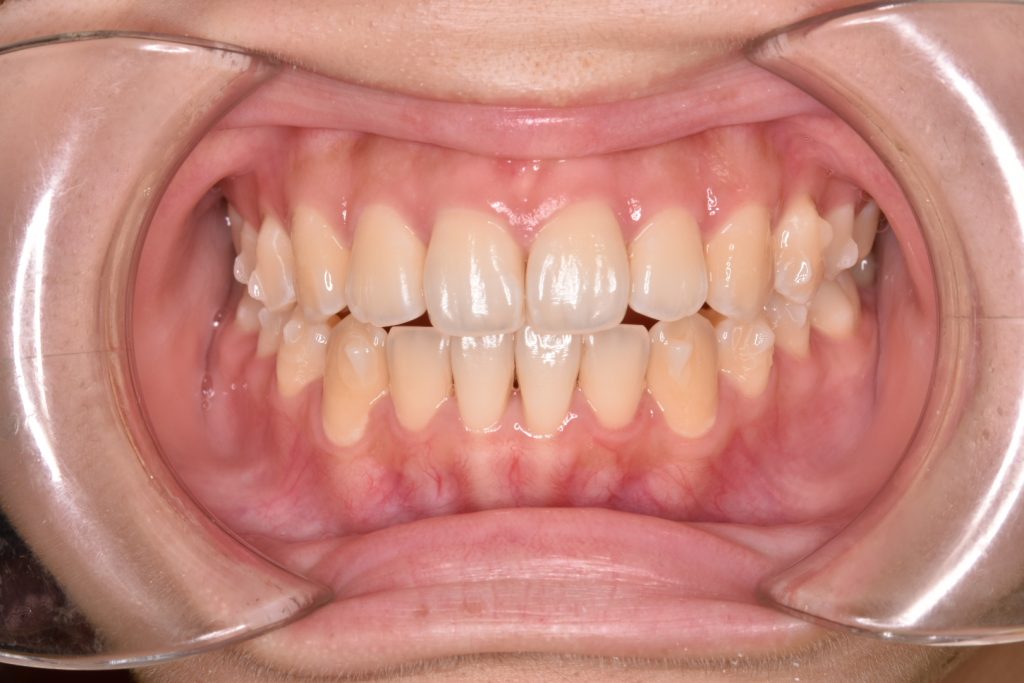

初診時

前歯が空いていて、奥歯でのみ噛んでいる状態です。ガタガタも認められます。